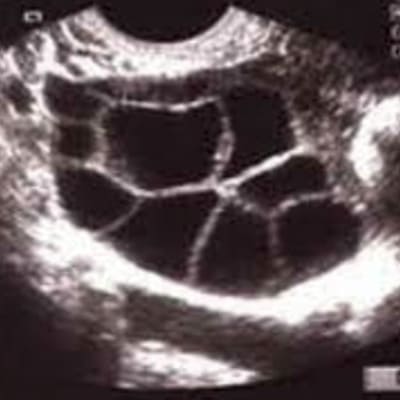

Esto se realiza por medio de la aplicación de hormonas subcutáneas diariamente , así como la vigilancia de la misma por medio de seguimiento folicular por medio de ultrasonidos endovaginales seriados.

Procedimiento que consiste en extraer los óvulos del cuerpo, por medio de una aspiración que se hace vía vaginal bajo visión por ultrasonido.